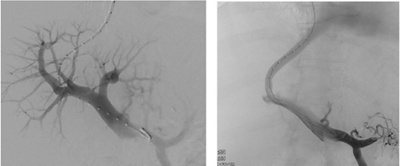

Zur Senkung des Pfortaderdrucks besteht die Möglichkeit einer minimalinvasiven Anlage einer künstlichen Kurzschlussverbindung zwischen Lebervene und Pfortader (TIPS, transjuguläre intrahepatische portosystemische Shunt-Anlage). Dieser Kurzschluss entlastet den Pfortaderkreislauf und führt zur Rückbildung der hierdurch entstandenen Folgeerkrankungen. Ein solcher Eingriff kann angezeigt sein bei ausgeprägten Krampfadern sowie bei auf medikamentöse Therapie resistentem Aszites.

Minimalinvasive Anlage einer Kurzschlussverbindung (TIPS) zwischen Lebervene und Pfortadersystem zur Senkung des Pfortaderdruck.